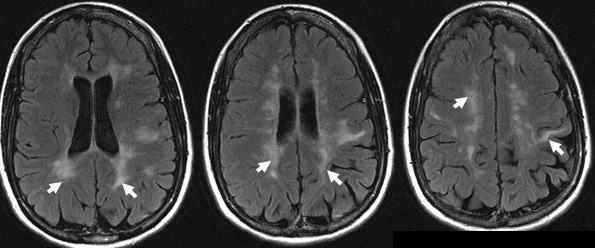

43+ White Spots On Brain Mri Ms UK. The white spots in the brain may indicate old age or areas which have been damaged.other tests may need to be done such as visual evoked potential i had a mri and the results was i had white spots on the brain. The white spots are called lesions and can an indication of ms.

Mri scans may reveal white matter lesions in young persons with migraine. Mri with contrast dye can indicate ms disease activity by showing a pattern consistent with inflammation of active demyelinating lesions. Ms learn online is the national ms society's online educational webcast series. With magnetic resonance imaging, doctors can use the lesions to track the progress of the condition.